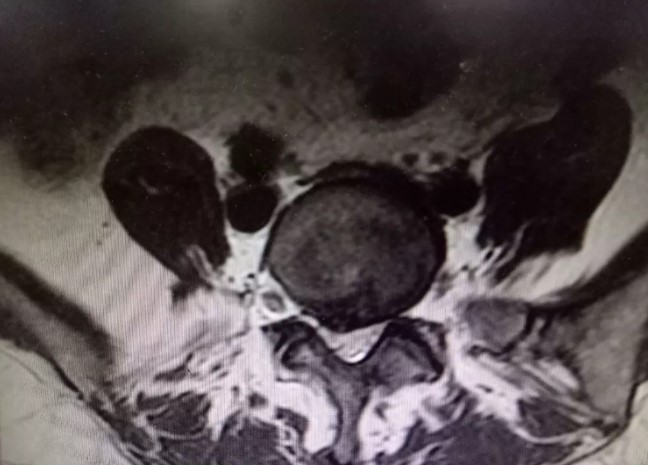

腰椎MRI如下图

【诊断】腰椎间盘突出症